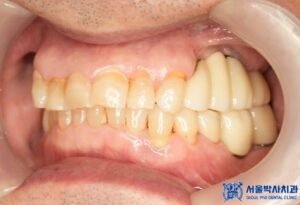

치료 마무리 후 사진입니다.

최종 보철물 세팅 이후 환자분께서는 불편함도 없었고,

교합 체크를 위해 다시 내원하셨을 때도

“음식 씹을 때 너무 편하고, 교합도 잘 맞는다”고

만족해하셨습니다.